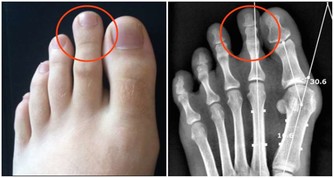

5、手足麻木

肝藏血,可以滋養人體的筋膜,使之活動自如。如果肝的氣血不足,則手足麻木、屈伸不利,甚至痙攣。另外,指甲和趾甲也是筋延伸到體表的部分,所以肝的氣血不足,還會表現為爪甲脆薄、顏色淺淡、變形脆裂等。